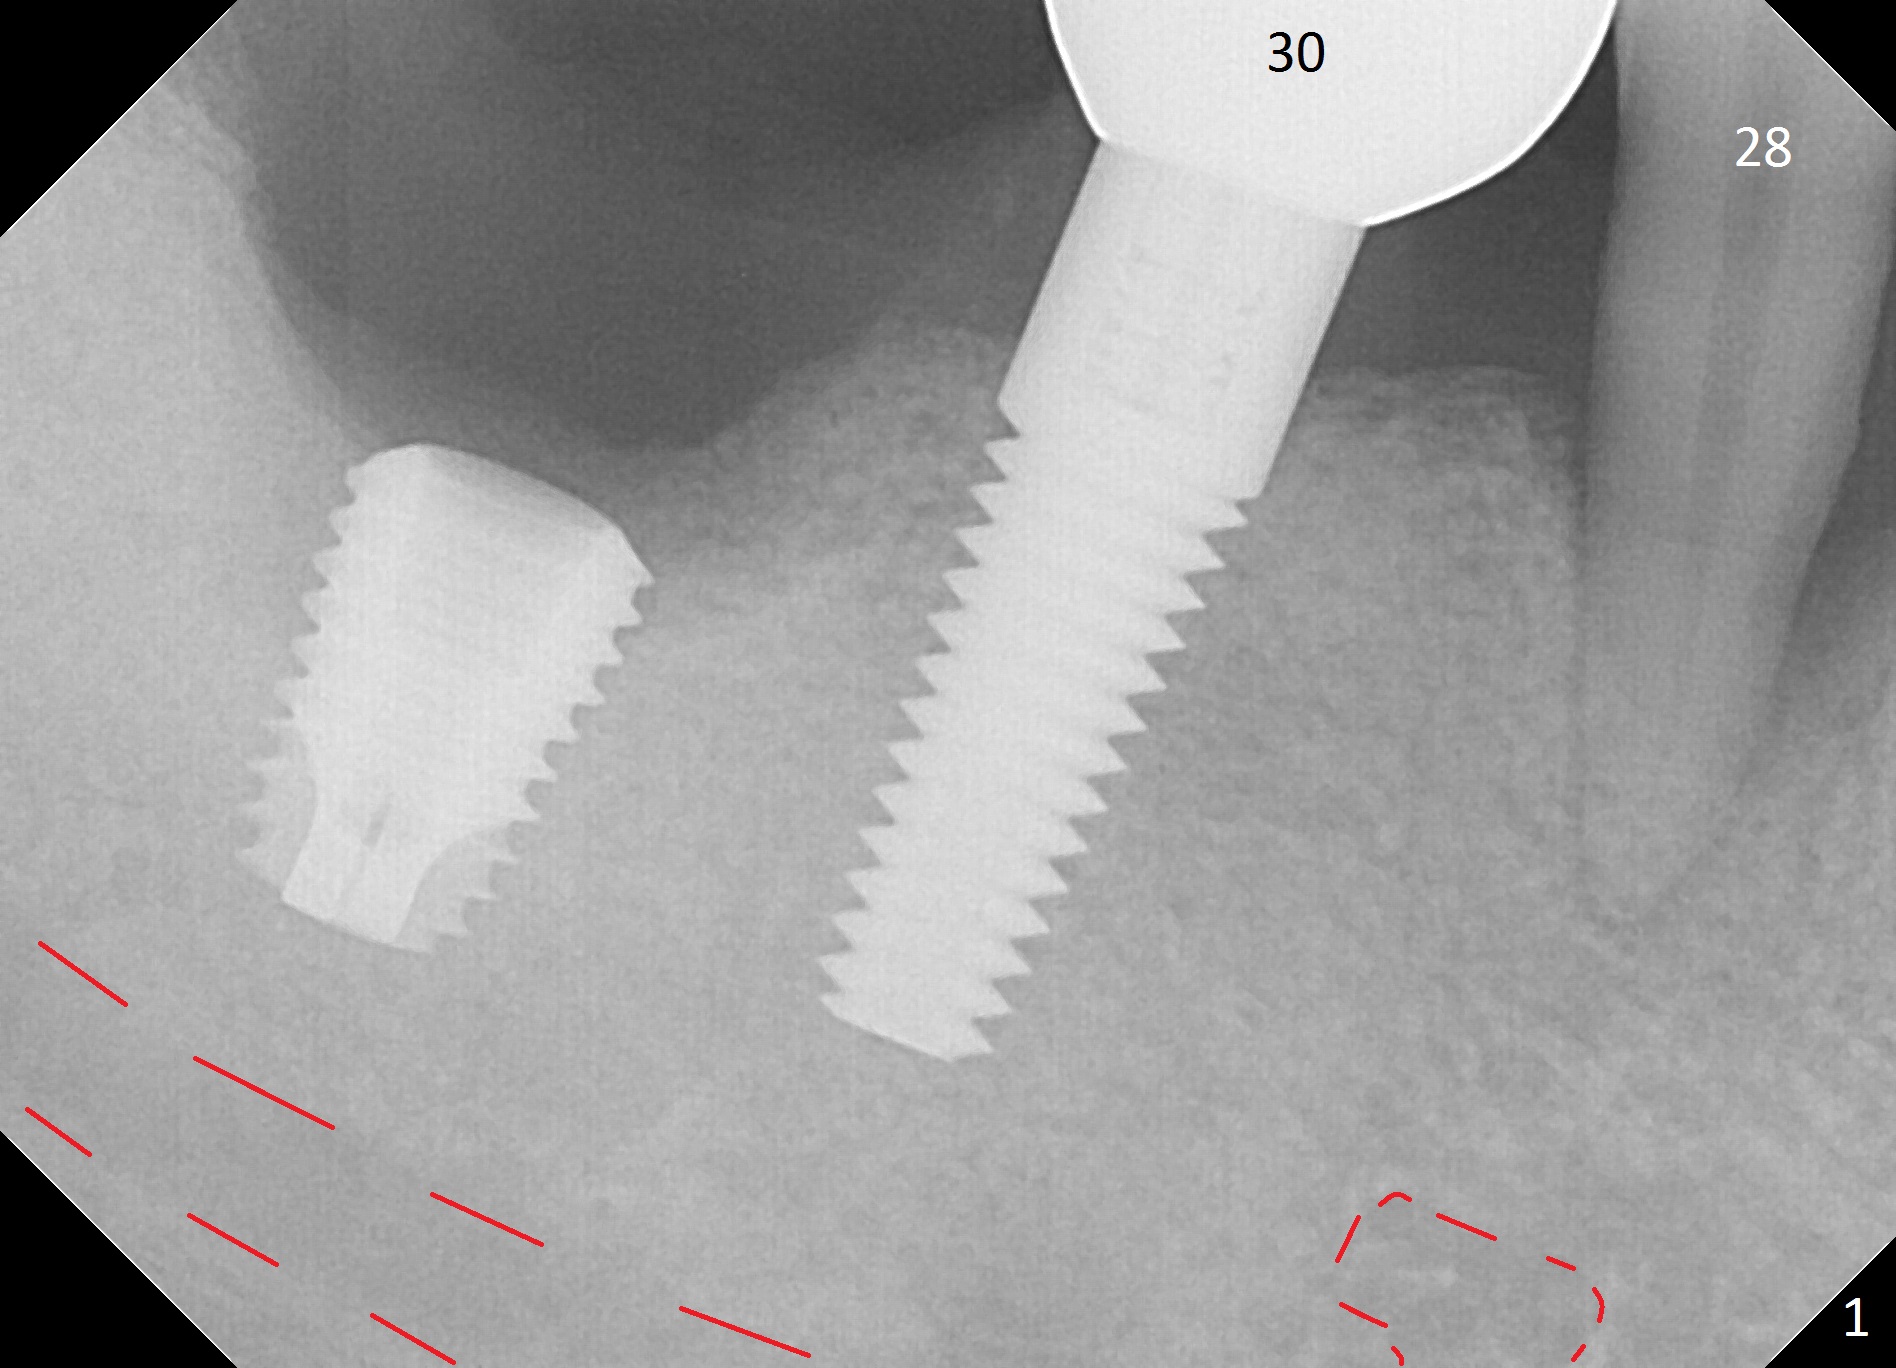

A 44-year-old man will return for #28 extraction and immediate implant 2-3 months after removal of the implant at #31 (Fig.1). After Clindamycin treatment, start osteotomy in the middle of the lingual wall of the socket (Fig.2,3 red line) with 1.6 mm for 13 mm (from oblique to straight). Take PA to determine clearance from the Mental Loop (Fig.1 red dashed line). If the trajectory is right, use 3.3 mm Magic Drill (MD) and possibly 3.8 mm one for short distance, since the bone density near the socket 700 units, while apically 100 units. Or use a 4x11 mm IBS dummy implant instead of 3.8 mm MD. An angled abutment may be used (Fig.2). Also prepare UF in case the gingiva is thick.